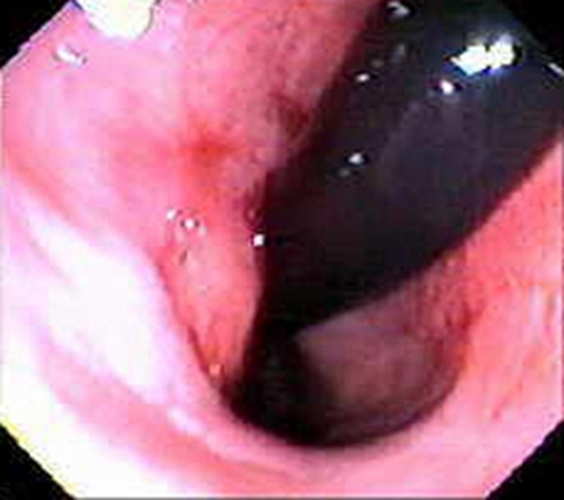

乙狀結腸癌潰瘍型症狀